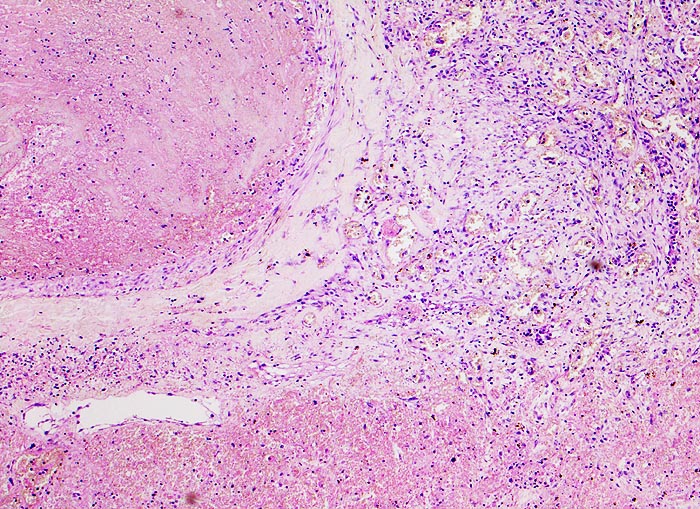

Makroskopisch bilden sie ein Dreieck mit der Basis an der Pleuraoberfläche, sind leicht erhaben, dunkelrot gefärbt und induriert. Innerhalb von 48 Stunden beginnen die Erythrozyten zu zerfallen und der Infarkt wird von aussen her narbig organisiert.

• Scharf begrenzte dreiecksförmige hämorrhagische Nekrose des Lungenparenchyms.

• Lungengerüst erhalten im Randbereich der Nekrose, nicht mehr erkennbar im Zentrum.

• Abgeblasste Zellkerne in der Nekrosezone.